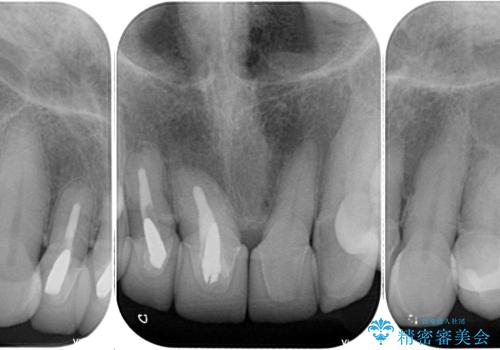

- 前歯のセラミックが欠けたり色調が不揃いであったりすることを気にして来院された患者様です。

20年以上前から、むし歯になったり詰め物が欠けたりする度に部分的に処置を行ってきたそうですが、この際統一感のある前歯にしたいとのことで、上顎前歯9本をオールセラミッククラウンによる補綴治療を行うこととしました。